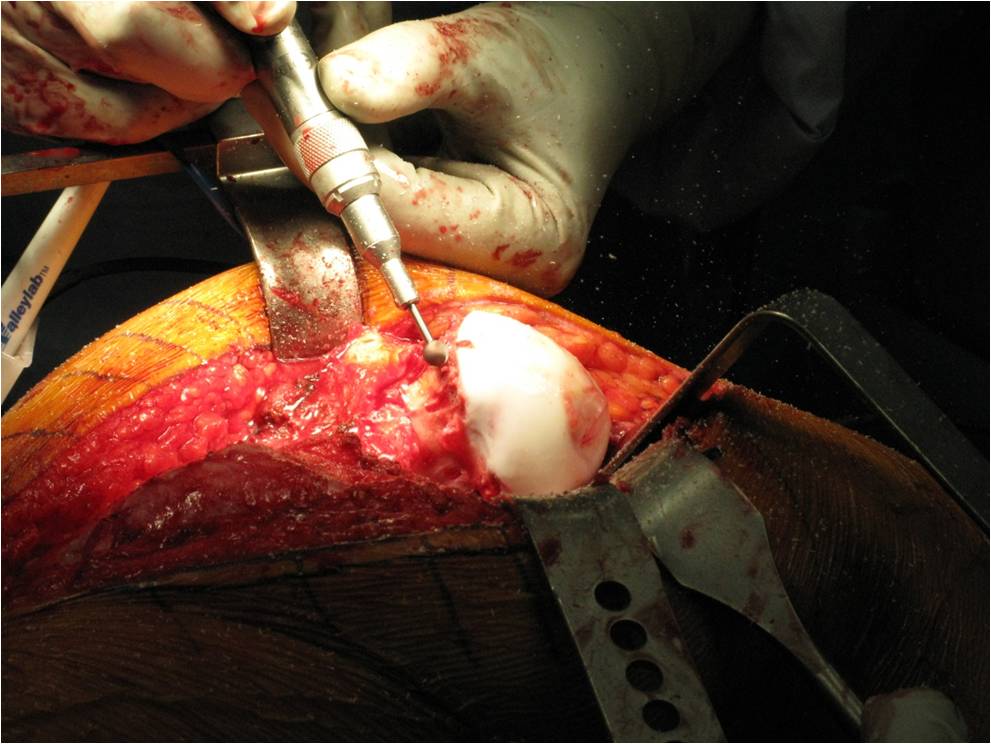

- Surgical hip dislocation (SHD) An important role is played by SHD, also called the modified Dunn procedure. ...

How to secure epiphysis to femur?

One or two screws are placed through the skin through a small incision into the femoral head to secure the epiphysis to the femur. Open surgery – This surgical procedure is used for patients with unstable SCFE to align the epiphysis on the femur and attempt to prevent the loss of blood flow to the femoral head.